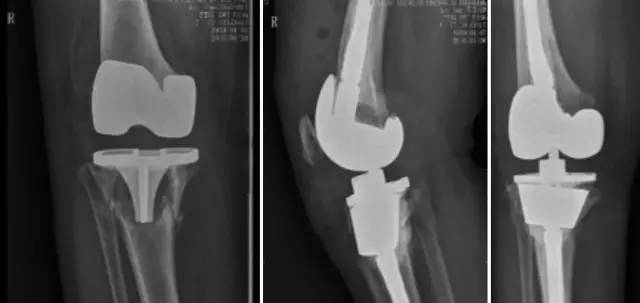

铰链式人工膝关节置换手术(HK)膝关节周围韧带严重破坏

国内首例膝关节置换术后Felix IIB型胫骨假体周围骨折翻修术